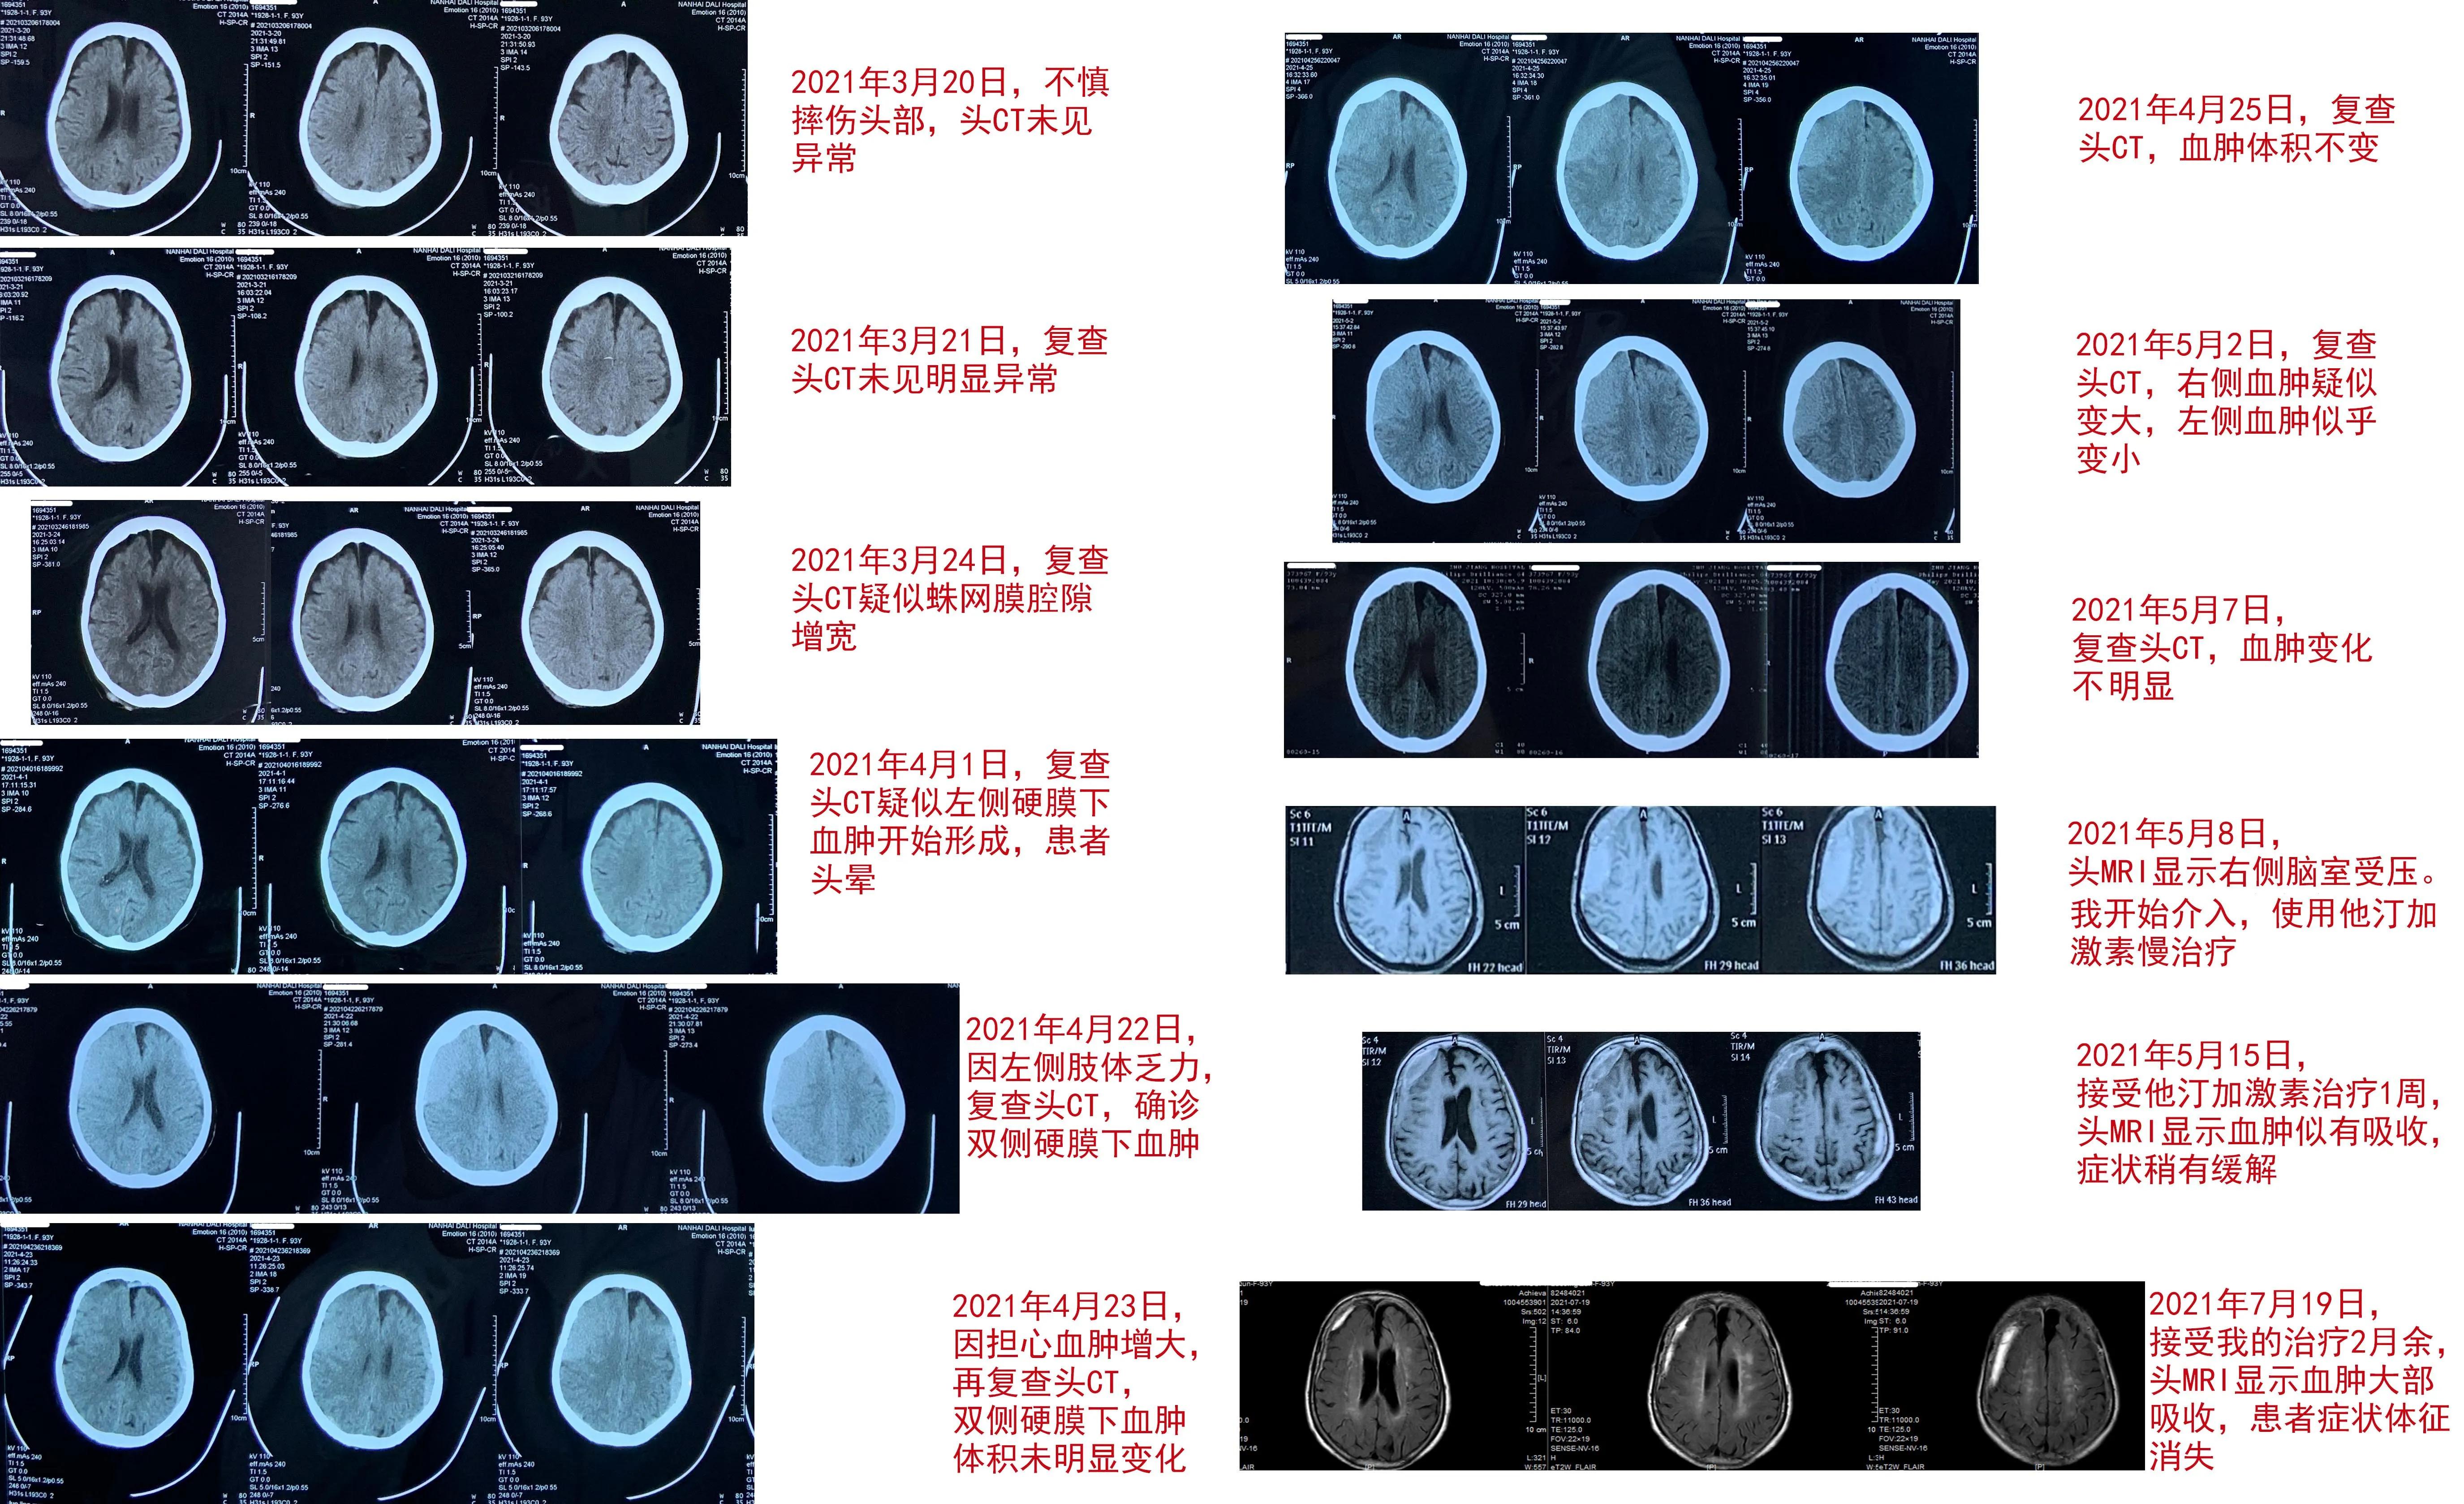

患者LMQ,93岁,是一名安逸的老太太。她平时身体很好,凡事都亲力亲为。今年3月20日,因为自己洗澡,摔了一跤,头破血流的。家人平时非常孝顺,这下都慌了神,在几天内,先后给做了3次头CT,以确定是否有颅内出血,结果都没有明显的异常发现,不禁松了一口气。但约半个月后,老人家开始头晕,复查CT,仍然没有明确颅内有异常,但仔细看,好像左侧形成了硬膜下血肿。套用江湖老话 “没有无缘无故的爱”,实际上也 “没有无缘无故的硬膜下血肿”。显然外伤是导致这个血肿的原因。再过20多天,老人出现左侧肢体无力,终于确诊为硬膜下血肿,多数医生都建议手术。她的家人担心高龄老人禁不起手术折腾,一片慌乱。但是,他们看老人除了走路不能像以前那样走远之外,精神意识完全正常,起居也未受到明显的影响,转诊到某著名神经外科。该医院的神经外科医生听过我的课,向家属介绍了我,邀请我过去面诊。说实在的,自从我从事神经重症专业以来,我经常出去会诊,但都是为重型脑损伤患者诊疗,还真没有专门为慢性硬膜下血肿患者会过诊。我跟这位神经外科朋友说,我可以在电话里会诊,不必远行。但我的朋友却说,家属很相信我,一定要面诊。我连夜赶到这家医院时,老人家因为白天在保姆扶助下走了一小段路,有点疲劳,已经入睡。我不得不将她唤醒。看她精神状况尚好,饮食无碍,就详细问病史,仔细查神经体征,查看影像学和治疗记录,作出短时间内应该不会出现脑疝判断后,决定应用立普妥加地塞米松治疗方案。由于是面诊,我可以详尽地向家属及同行朋友介绍我的治疗理念以及治疗中需要注意却极其容易为患者和家属忽略的细节,并交待了可能发生的副作用和应对方法。我鼓励他们,我用药物治疗过16位90岁以上的硬膜下血肿超级老人(≥90岁),战绩是100%治愈。LMQ老人被我治愈的概率也非常大,这极大鼓舞了家属和患者。我的方案很简单:每天1粒20mg立普妥,一直服用到血肿吸收为止;同时加服4周地塞米松,从3片/次,1天1次,持续1周开始,用4周时间逐步减量到停药即可。出于信赖,老人的家人并不因为我给出这么简单的方案而觉得我在慢待他们,反而极其感谢我为他们提供了非手术方案。我们相约1周后复查影像学,并请医生将患者治疗中的不适反应及时告知我,我来帮助处理。结果,治疗第三天,患者即出现睡眠困难,我判断跟激素有关,给予对症治疗后缓解;治疗1周,不仅患者的左侧肢体力量得到改善,头晕减轻;而且头磁共振检查验证了她的血肿开始减少,虽然减少得还很少,但已经有了希望,再次激励了患者和家属。2周后,医生朋友发来老人家在花园里独自行走的视频并解释因为疫情缘故,老人家没能及时复查头MRI,但承诺尽快去复查。今天,我才见到老人家治疗约2个多月后的磁共振复查影像:我欣喜地发现患者的血肿已近乎完全吸收,神经症状和体征也完全消失……

在这平凡的夜晚,我在北方这座中国神经外科发源之城中独自欣赏着着老人历次治疗的影像变化(图),不禁给自己倒了杯酒,自斟自饮地为这位我并不熟悉的老人家的康复庆贺,为慢治疗再次被成功验证而庆贺。这就是医生的快乐。这种快乐也许永远都不被人理解,也无需被理解……